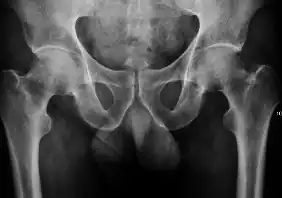

![Figure 2A. Normal hip.[1]](./X-ray_of_measurements_on_a_normal_hip.jpg)

![Figure 2B. Hip dysplasia.[1]](./X-ray_of_measurements_in_hip_dysplasia.jpg)

X-ray of infants should be obtained with the pelvis in neutral position with the lower limbs held in neutral rotation and slight flexion.

- Hip dysplasia

Despite the widespread of ultrasound, pelvis X-ray is still frequently used to diagnose and/or monitor hip dysplasia or for assessing other congenital conditions or bone tumors.[1]

The most useful lines and angles that can be drawn in the pediatric pelvis assessing DDH are as follows:[1]